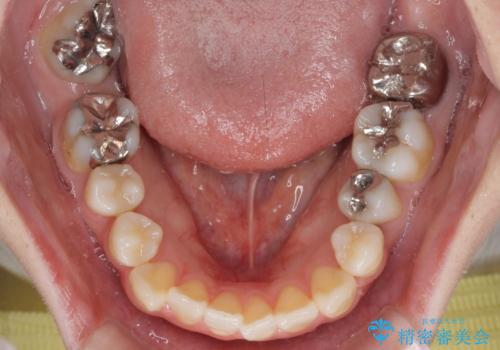

- 口元の突出感と奥歯の欠損を気にして来院された患者様です。

口元の突出感改善には、上下左右の第一小臼歯4本を抜歯し、奥歯の欠損部には矯正治療の途中でインプランを埋入していくこととしました。

矯正治療の後半にインプラント埋入を行うことで、トータルの治療期間を短縮することができました。